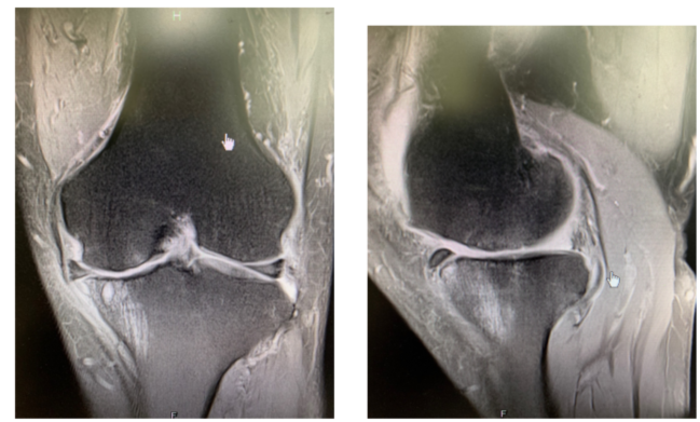

四、 影像学检查:

膝关节X线片示左膝关节内侧间室间隙变窄,关节面硬化。

膝关节MRI片示左膝关节内侧股骨平台及股骨髁表面软骨变薄,内侧半月板损伤,内侧胫骨平台下方骨髓水肿并囊样改变。